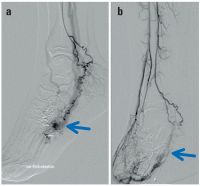

Phlebographie

Abbildung 3a-b: Phlebographie: Direkte Punktion der venösen Malformation (a); aszendierende Phlebographie mit Darstellung des venösen Poplitealaneurysmas (b).

Keywords: GefäßmedizinPhlebographievenöse Malformationvenöse Poplitealaneurysma

Angiographisches Bild

Abbildung 7a-b: Angiographisches Bild (a) vor und (b) nach Ethanolembolisation. Der Nidus (Pfeil) mit Abstrom nach proximal ist nach der Embolisation ausgeschaltet.

Keywords: Angiographisches BildEthanolembolisationGefäßmedizinNidus